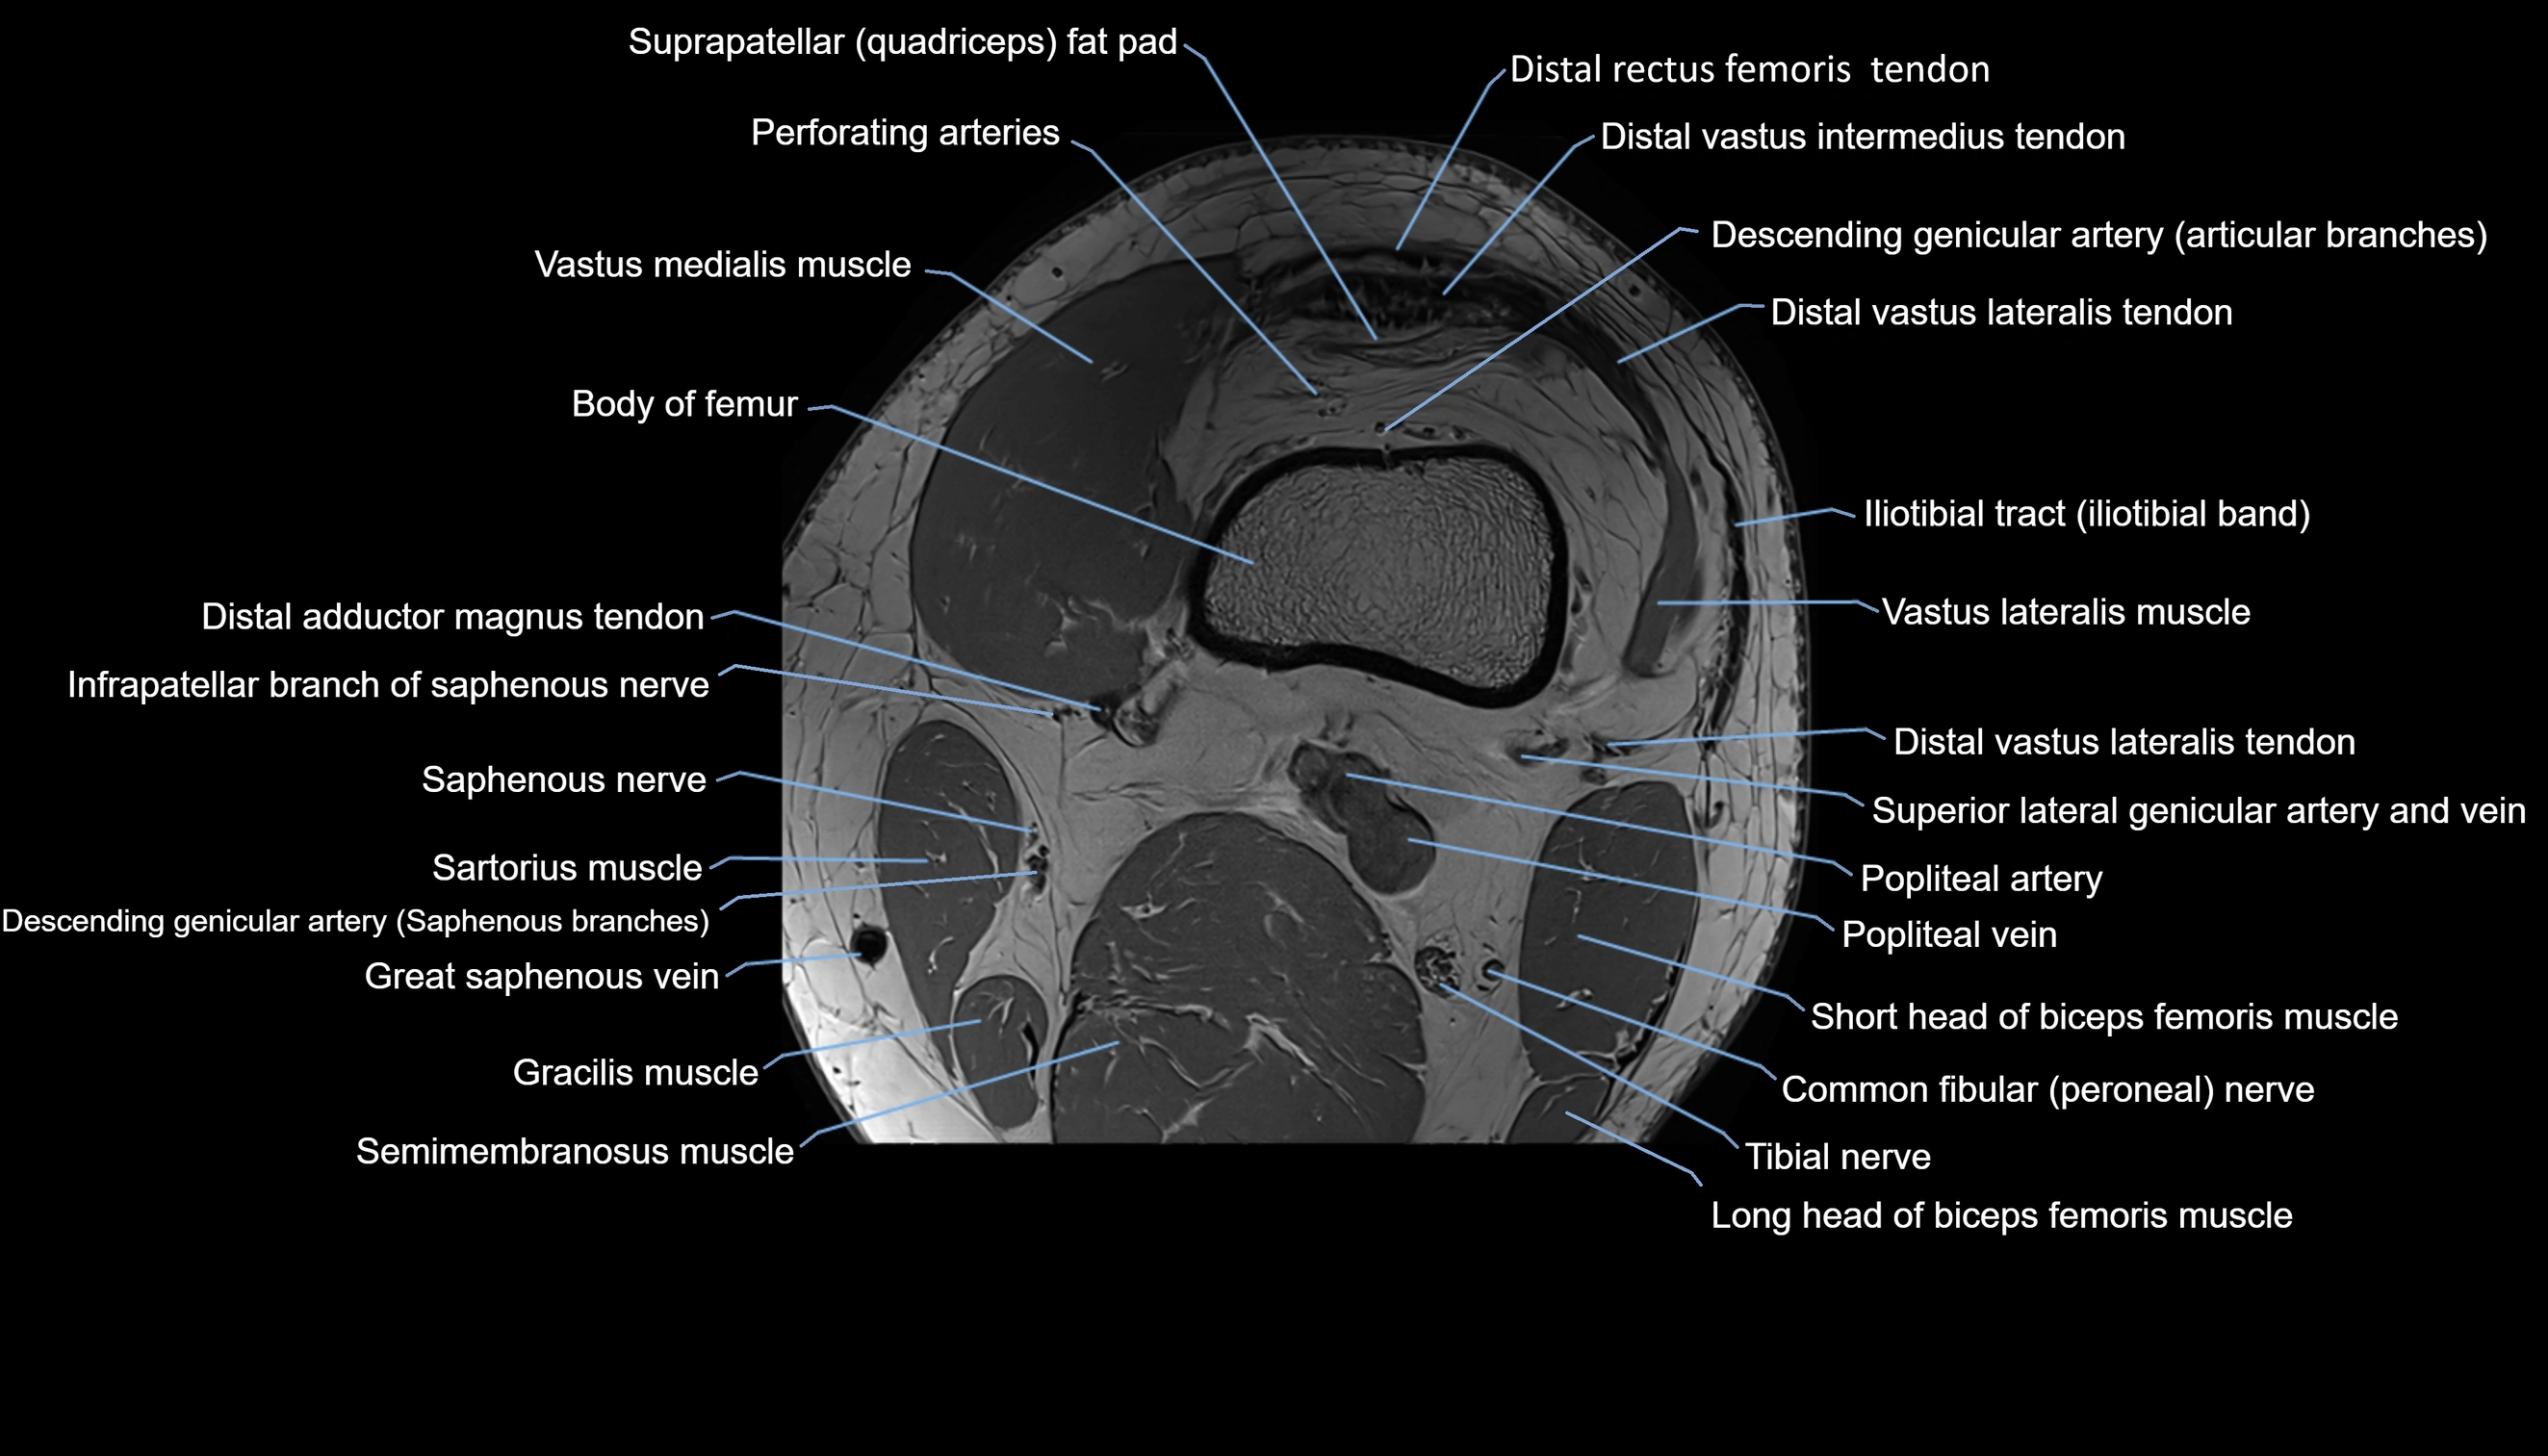

- Body of femur

- Descending genicular artery (Articular branches)

- Descending genicular artery (Saphenous branch)

- Distal adductor magnus tendon

- Distal vastus intermedius tendon

- Distal vastus lateralis tendon

- Infrapatellar branch of saphenous nerve

- Perforating Arteries (Knee joint)

- Popliteal artery

- Popliteal vein

- Sartorius muscle

- Semimembranosus muscle

- Suprapatellar fat pad

- Tibial nerve

- Vastus lateralis muscle

- Vastus medialis muscle